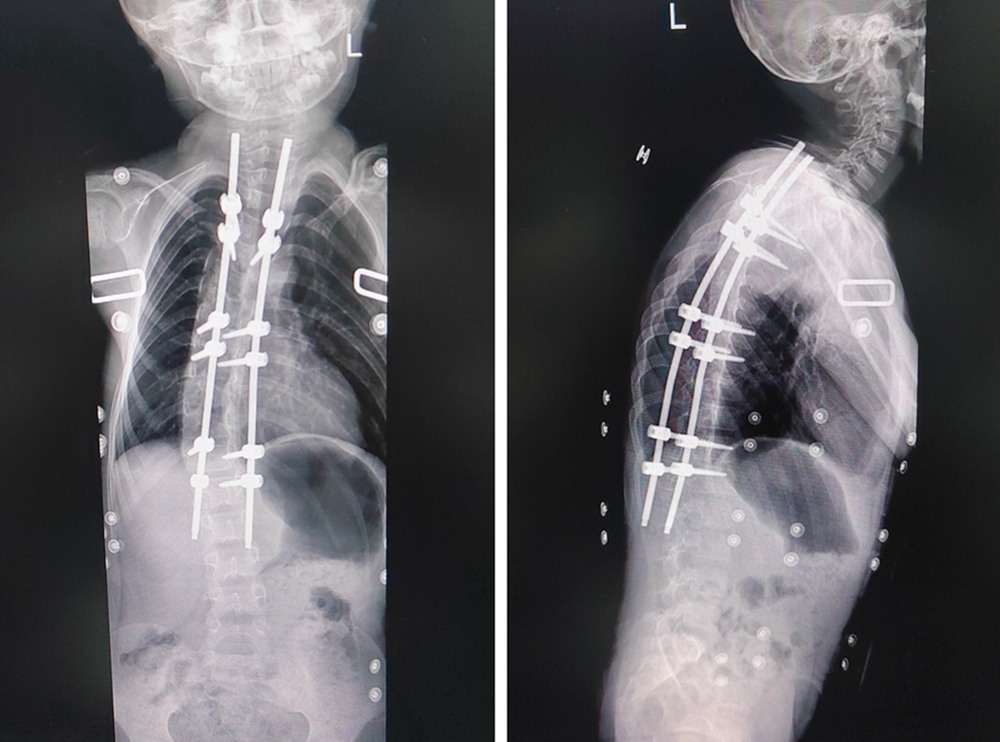

术后影像资料

术前术后对比

脊柱有大于等于10度的侧方弯曲即为脊柱侧弯,次仁加央的脊柱侧弯达到了70度。若不手术,他的脊柱侧弯角度还将增大,外观畸形也会更加明显,甚至严重影响心肺功能和生长发育。

术前,常德一医骨科、儿科、麻醉科等多学科专家为次仁加央进行会诊,制定周密的治疗方案,运用3D打印技术制作次仁加央的脊柱模型,直观反映脊柱病变,协助制定精确的手术计划。1月14日,在术中神经电生理监测全麻下,次仁加央顺利接受脊柱侧弯矫正手术。